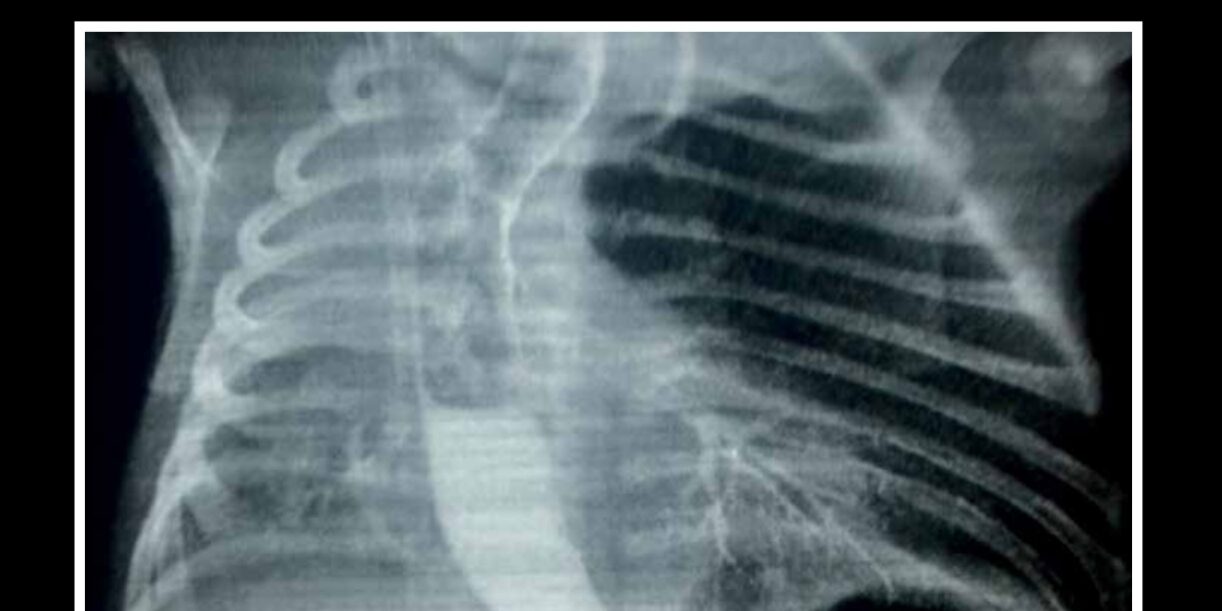

Pseudoaneurisma de la aorta torácica: tratamiento endovascular, reporte de un caso

- Autor: Dr. Maurizio Bassino Pinasco, Dr. Ricardo Arce Cano

Pseudoaneurysm of the thoracic aorta: Endovascular treatment, a case report

- Author: Dr. Maurizio Bassino Pinasco, Dr. Ricardo Arce Cano